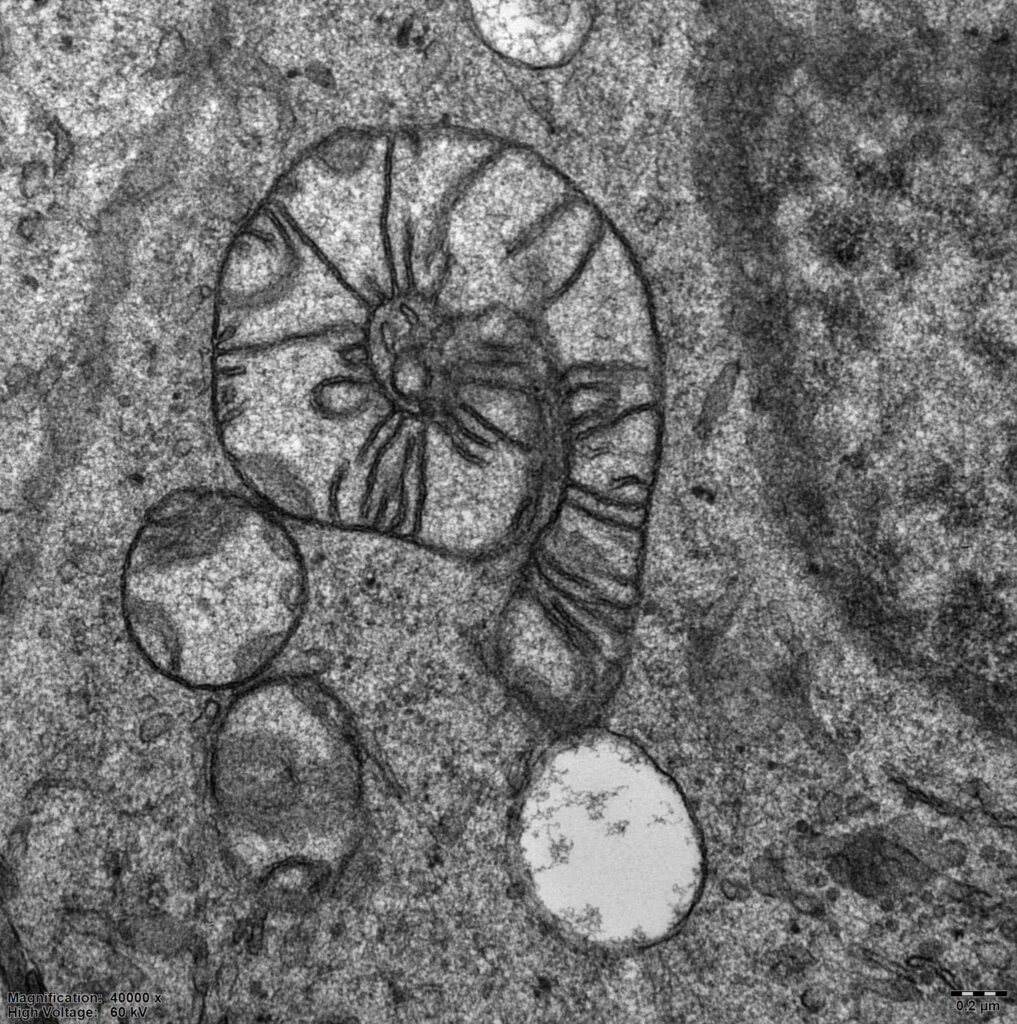

Studujeme fyziologii mitochondrií – hlavních producentů energie v buňkách na molekulární úrovni. Využíváme jak zvířecích modelů, tak buněk pacientů s různými dědičnými mitochondriálními poruchami. Zabýváme se především výzkumem v těchto oblastech:

- Studium tvorby mitochondriálních proteinových komplexů a superkomplexů.